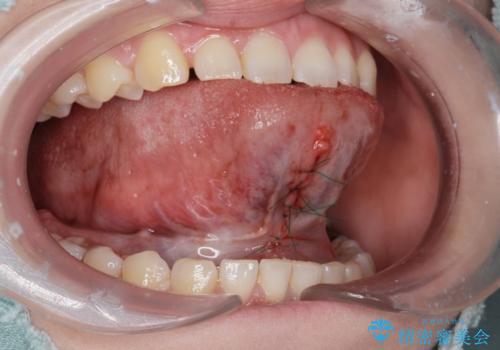

- 舌小帯を切りたいとの事で来院。

麻酔を行い、舌小帯切除術を行いました。

舌の可動域が広がりました。

舌小帯切除は1日で処置が終わります。

1週間後には抜糸をする必要があるので通院は2回で終了します。